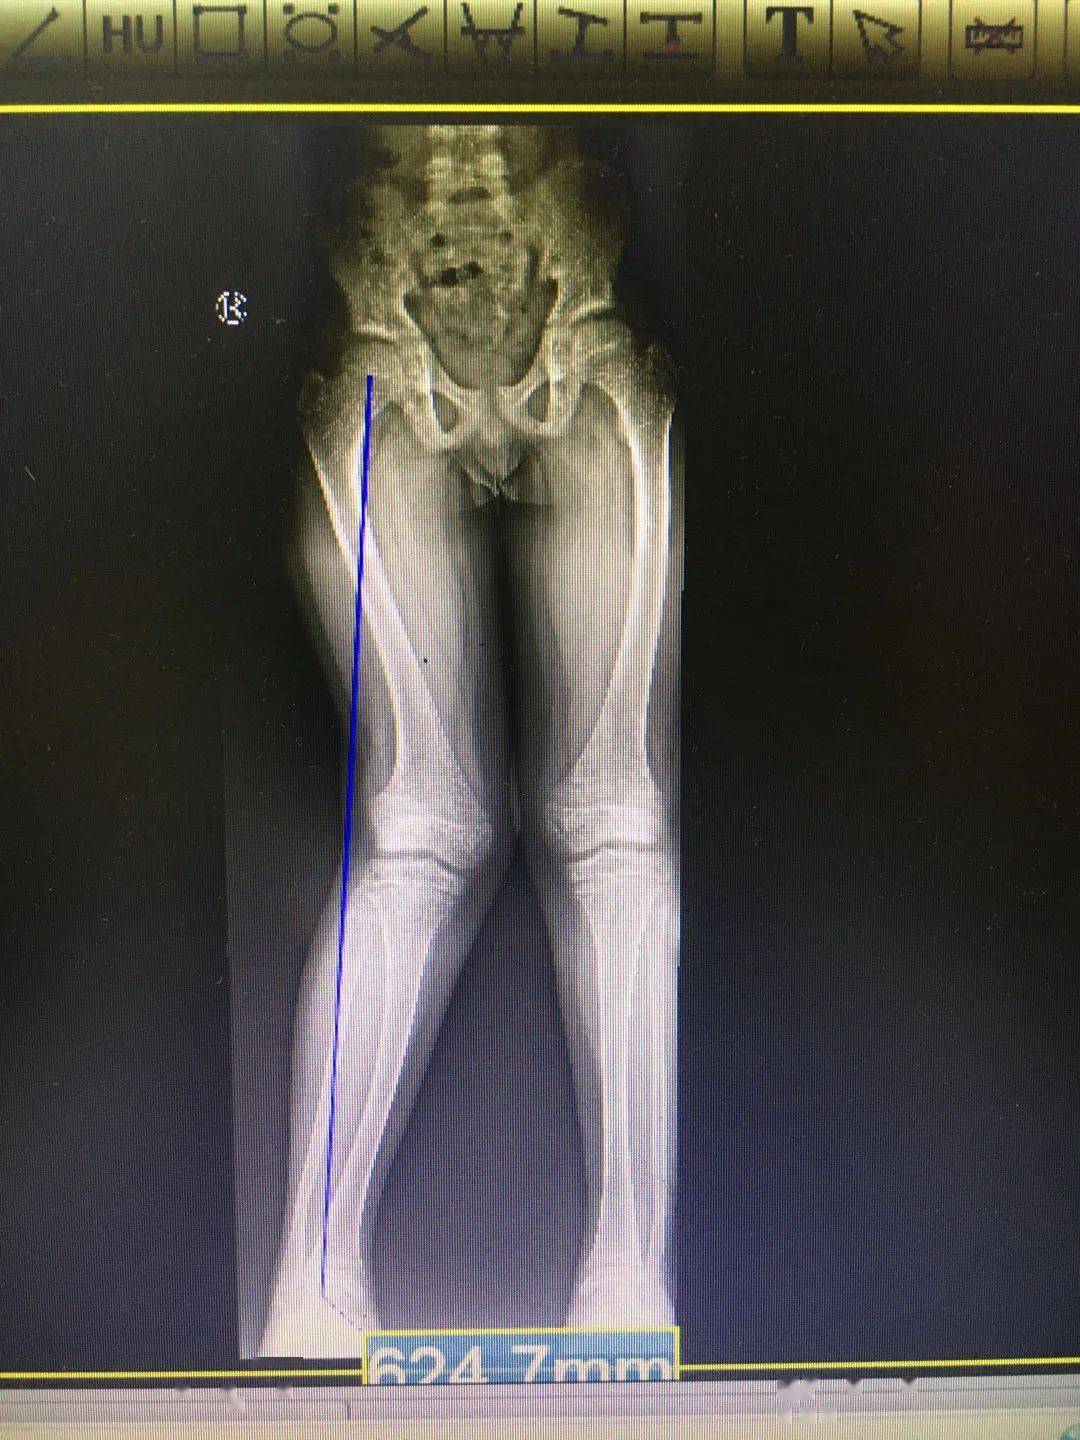

花了家里16万切断双腿骨头,只为增高7厘米,如今与后遗症为伴

图片尺寸500x667

高三男子因身高矮小自卑,花16万断骨增高7.

图片尺寸500x592

2014年,北京小伙花16万断骨,只为增高7厘米,如今与后遗症为伴

图片尺寸871x571